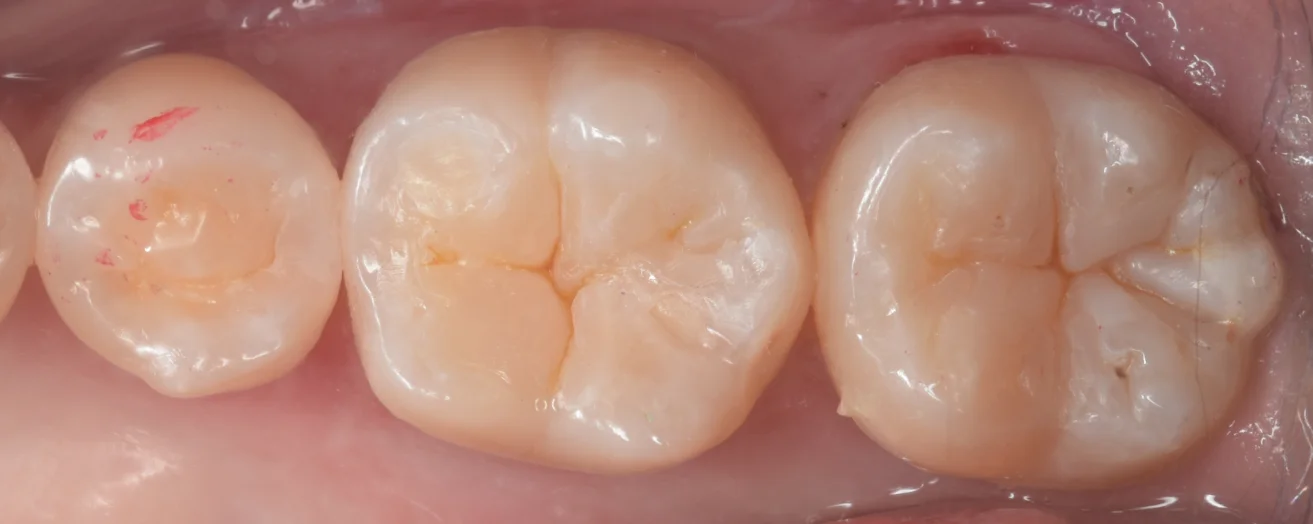

そして詰め終わったのがこちらになります。

患者さんは歯科医師ということも合間って、非常に喜んでいただけました。

違和感なく仕上げられたかと思います。

噛み合わせの調整も最小量で済んだかと思います(●´ω`●)